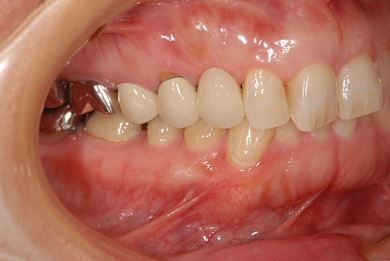

治療前

• 治療前